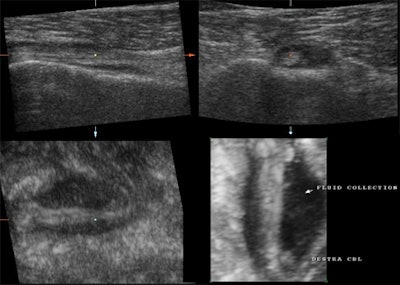

![]() |

| Multiplanar and 3D imaging of a completely ruptured biceps tendon. This is a study of an elderly patient who, after having lifted a heavy load, presented with weakness of the arm and swelling at the level of the middle of the humerus. One must follow the length of the biceps tendon from its origin to its insertion with the muscle. With acute traumatic rupture of the biceps tendon, the muscle contracts and collapses upon itself distally while the tendon retracts as in the above case. All planes demonstrate a fluid collection within the biceps sheath, the absence of any tendon fibers throughout the fluid collection, and the collapsed biceps muscle beneath. |